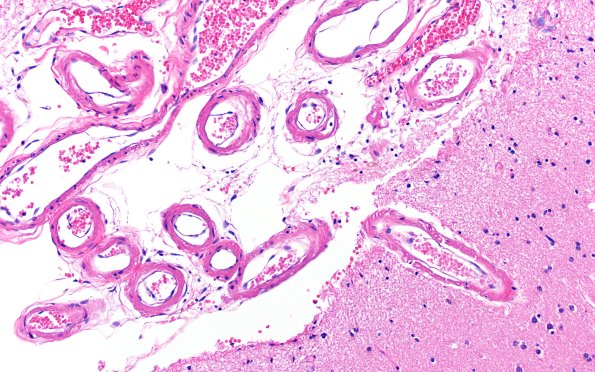

Washington University Experience | NEURODEGENERATION | Pick Disease | 11C4 Pick Dz (Case 11) N14 H&E 20X

The subarachnoid vessels continue to be prominent. The vascular walls contain amorphous material (later shown to be amyloid). Somewhat unusual is the collection of “double-barrel” telescoped vessels in large numbers within the parenchyma. In this site there is only mild neuron loss and pallor. (H&E)